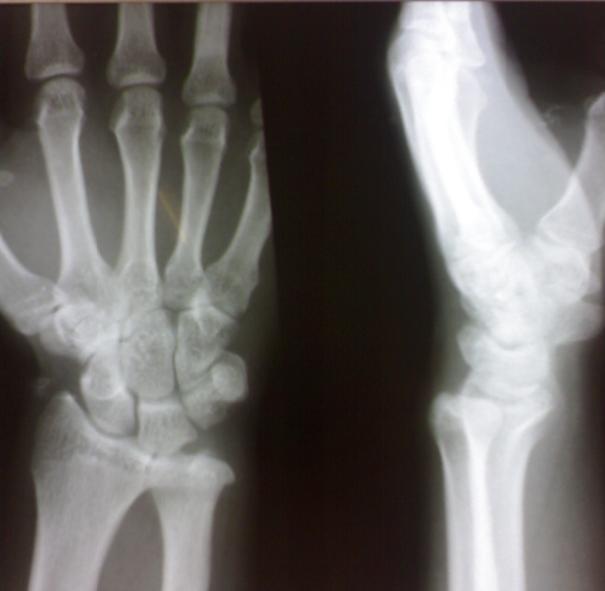

这个和上面类似,但是手外科的病人,病人功能可 脱位不明显 余(—)。

第一例下尺桡关节间隙略宽,可考虑半脱位表现。第二例表现为退变及软组织骨化改变,考虑为陈旧性外伤所致

一、此二例正侧位片投照均不标准,正确的投照体位是肘关节曲约90度,高度最好与肩平齐,前臂尺侧贴紧台面,这样投照出来的位置才是标准的,并且这样投照出来的影像基本不会出现向后半脱位的情况,因为本位置是后半脱位的复位体位。

二、下尺桡关节后半脱位个人认为是不能用x线和ct来诊断的,因为下尺桡关节是个活动度很大的关节,况且还有下尺桡关节不稳定的情况(活动更大,甚至正位间隙都可以超过3-4mm)随不同体位有不同的表现,此二例如果没有看错的话,投照时肘关节是可能是伸直的,而且肘部过于紧张,前臂尺侧没有贴紧台面。

三、这种影像是有特征的,1、尺骨远端向后翘出2、正位像尺骨茎突重叠于尺骨头中部(正常投照时重叠在外侧缘)3、侧位像尺骨茎突亦重叠于中部(正常投照时重叠于后缘)4、正位像下尺桡关节间隙重叠(正常是有完整间隙的)

四、个人认为下尺桡关节半脱位诊断靠临床表现,碰到这种情况又不能确定是否按正确体位投照时要亲自检查患者下尺桡关节,看患者是否有压痛,关节活动度是否大(可用力向前后按压尺骨头),活动时是否有弹响、痛疼,还要嘱患者双侧旋转对比,看患侧尺骨头是否有异常翘起